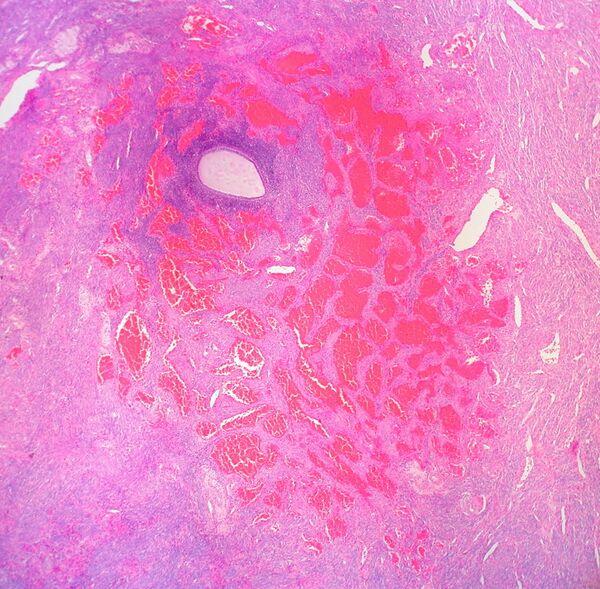

Гемангиома

Гемангио́ма (от греч. haima — кровь + angeion — сосуд + -oma) — доброкачественная опухоль, состоящая из самостоятельно инволюционирующих эндотелиальных клеток кровеносных сосудов[2].